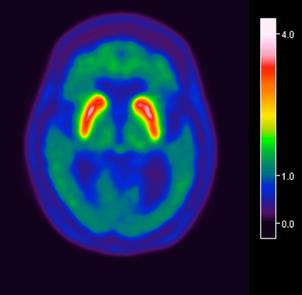

Femenino de 65 años, antecedente de hipertensión arterial de 20 años de evolución en control. Sin antecedentes familiares relevantes de enfermedades neurológicas. Acudió a consulta médica por deterioro progresivo en su capacidad motora y dificultades en las actividades diarias. Desde hace 2 años ha notado cambios en su marcha y en su habilidad para realizar movimientos finos con las manos principalmente del lado izquierdo, rigidez muscular, temblor en reposo siendo mayor del lado izquierdo y dificultad para iniciar y mantener el movimiento, especialmente al levantarse de una silla o al comenzar a caminar. Además, los familiares han observado que tiene una expresión facial inexpresiva y que su voz se ha vuelto más monótona. A la exploración física con expresión facial inexpresiva, temblor de reposo bilateral en manos de predominio izquierdo, rigidez muscular generalizada, más pronunciada en las extremidades superiores, bradicinesia evidente en la realización de movimientos finos de las manos, marcha festinante con pasos cortos y arrastrando los pies, reflejos osteotendinosos normales, no se observan déficits sensoriales. Se realiza adicionalmente la escala de Evaluación de la Enfermedad de Parkinson (UPDRS) con un total de 35 puntos, indicando moderada afectación de la enfermedad. Inicialmente se realiza una tomografía simple de cráneo, sin alteraciones estructurales, al no encontrar algún hallazgo se decide realizar posteriormente Resonancia Magnética Cerebral 1.5 Tesla: sin alteraciones estructurales significativas. Por este motivo y ante la alta sospecha clínica se realiza estudio de imagen molecular PET-RM con 6-[18F] FDOPA en equipo 3 Tesla en el cual se observa la disminución de la captación de la 6-[18F]FDOPA a nivel de putamen y caudado de predominio derecho evidenciando la degeneración dopaminérgica nigro presináptica a este nivel, con un patrón tipo 2 (Egg shaped) así como la mala definición de nigrosoma, estos hallazgos compatibles con enfermedad de parkinson. (Figura 1 y 2)

Figura 3. Reconstrucción mediante imagen molecular de imagen híbrida PET-RM 3T con 6-[18F] FDOPA observando disminución de la captación del radiotrazador a nivel de ambos putámenes en la región posterior, media y anterior así como en ambos núcleos ca dados de predominio derecho.

Figura 4. Reconstrucción mediante imagen molecular de imagen híbrida PET-RM 3T con 6-[18F]FDOPA observando captación adecuada y conservada del radiotrazador en el cuerpo estriado (ambos putámenes y núcleos caudados) en un paciente negativo para enfermedad de parkinson.

En cuanto al campo de los estudios de imagen convencional y de laboratorio no existe alguna prueba que pueda confirmar la enfermedad. Sin embargo, las imágenes de diagnóstico por métodos de imagen molecular del tipo no invasivas, como la tomografía por emisión de positrones (PET) en conjunto con un resonador de 3 tesla (RM 3T), pueden respaldar el diagnóstico de un médico, actualmente éste método tiene una sensibilidad diagnóstica de 95.4%, especificidad 100%, valor predictivo positivo del 100% y valor predictivo negativo del 87.5%. (5,6)